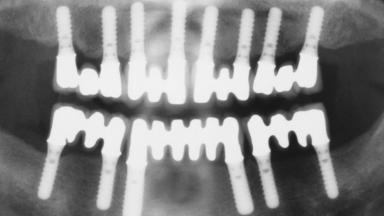

Immediate Loading of Eight Implants in the Maxilla and Six Implants in the Mandible and Final Restoration with Three-Unit and Four-Unit FDPs

Extensive scientific evidence has confirmed that immediately loaded implants with fixed full-arch provisional restorations can osseointegrate with success rates similar to conventionally or delayed loaded implants. A number of immediate-provisionalization techniques for edentulous jaws have been described. Some protocols differ when it comes to prefabricated provisional templates versus complete denture conversion; intrasurgical impressions versus direct relining; and cemented versus screw-retained provisional restorations. In this context, complete-denture conversion has been proposed for either intrasurgical impressions or direct relining. Another possibility is the utilization of a prefabricated provisional to be adapted either in the mouth (by direct relining) or in the laboratory (on a working model obtained from an intrasurgical impression).

# of Implants 14

Type of Implants One-Piece

Defining Characteristics Fully edentulous upper jaw to be rehabilitated with four or more implants

Modality 6+ implants with immediate loading